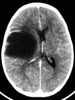

Desmoplastic infantile ganglioglioma